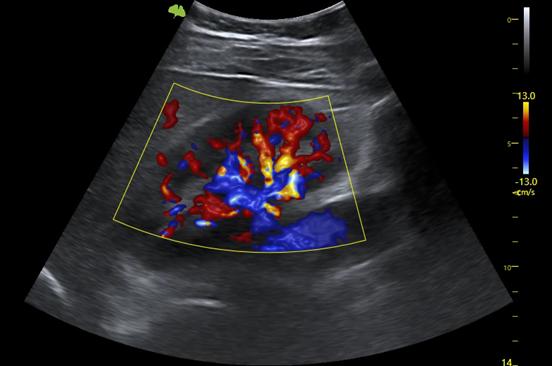

4. VLuminous Flow: Hình ảnh trực quan 3 chiều về dòng chảy máu giúp hiểu rõ cấu trúc của dòng chảy máu và các mạch máu nhỏ một cách trực quan.